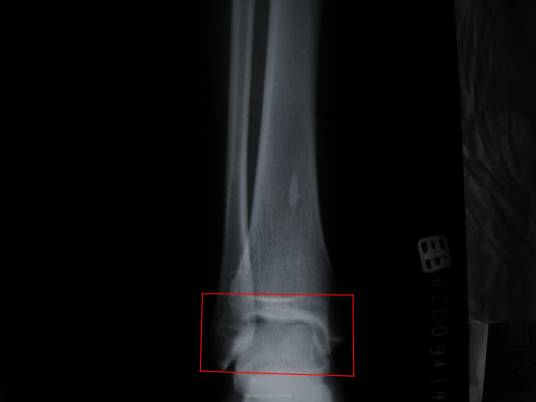

人体长骨的构造有如吸管,中间是空的。当骨头伸直较为强韧,弯曲时较为脆弱。而其中最软的部分就是位于骨头两端的连接处,称作海绵骨。如以椎骨为例,其四周是坚硬的骨骼又称皮质骨,内部里的是建筑物的梁柱部份就是海绵骨。海绵骨及皮质骨的功能是不同的,例如腕骨及大腿骨的中间只有皮质骨,但愈往两端则出现海绵骨,椎骨时的海绵骨占大部分,四周有一层薄的皮质骨。并且他是十分柔软且脆弱的。较强的外力很容易使海绵骨断裂,从而造成我们熟知的骨折。但是经过后天的人为锻炼可以避免这方面的伤害的,如硬气功。